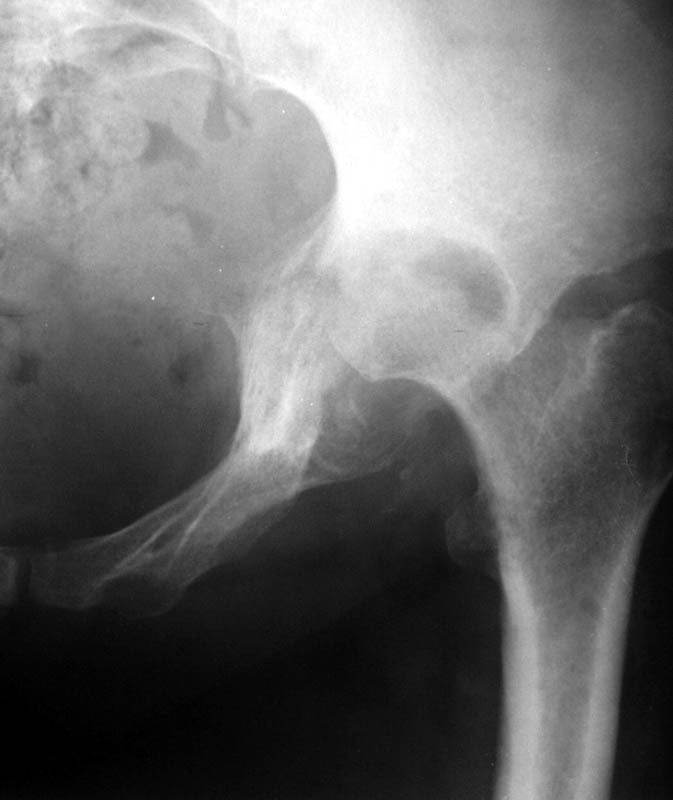

Женщина, 45 лет. В марте перенесла левосторонний коксит неизвестной этиологии. Специфику и онкологию исключили.

Интраартикулярных инъекций не было. Сейчас процесс клинически и рентгенологически - стабилизировался. Состояние вполне удовлетворительное.Предполагается тотальное эндопротезирование с пластикой полости аутокостью. Возможна ли бесцементная <чашка>? Заранее благодарю! С уважением,А.В.Владзимирский

Пртезирование через пол года после коксита закончившегося лизисом сустава, который на снимках выглядит как гнойный? Что значит неизвестной этиологии?

Уважаемый коллега! Последняя версия - мы пролистали ренгенологическую книженцию-так картинка вполне подходит под сустав Шарко (neuropatic joint ). В тазобедренном суставе патология редкая (но меткая). Ищите причину - варианты - нейросифилис, сирингомиелия, опухи спинного мозга (и выше тоже) компрессия спинного

мозга извне, рассеяный склероз, алкоголизм. А так-же : склеродерма ,Рейно,ревматоидный артрит, амилоидная инфильтрация нервов,и это не считая всяких менингеомиелоцеле,asymbolia,Riley-Day syndrom,и все возможные другие нейропатии. На данном этапе не спешите оперировать(протезирование протиопоказано при нейропатических суставах),проконсультируйтесь с классным невропатологом,сделайте МЯР головного озга и

весь позвоночник. И держите нас в курсе - случай крайне интересный :)